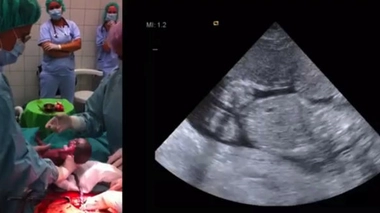

Donner la vie après la mort : le dilemme des naissances posthumes

A gauche, la mise au monde de l'enfant par césarienne. A droite, l'une des échographies réalisées avant l'accouchement. (source : clinique de Debrecen)